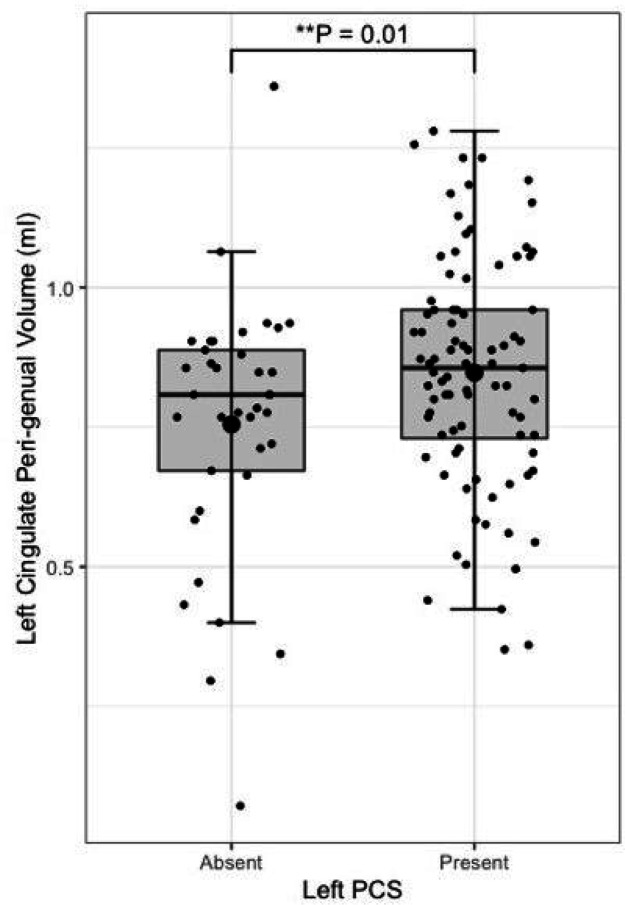

Presence of a left paracingulate sulcus was associated with reduced fractional anisotropy in the left cingulum (P = 0.02) bundle and the peri-genual (P = 0.002) and dorsal (P = 0.03) but not the temporal cingulum bundle segments. Left paracingulate sulcal presence was associated with increased left peri-genual radial diffusivity (P = 0.003) and tract volume (P = 0.012). A significant, predominantly intraregional frontal component of altered resting state functional connectivity was identified in individuals possessing a left PCS (P = 0.01). Seed-based functional connectivity in pre-defined networks was not associated with paracingulate sulcal presence.

Following quality control procedures segmentations were available for 125 subjects, (mean age 52.19, SD 5.12), see Table 1. The frequency of present to absent PCS was greater in the left (88/125) than right (71/125) hemisphere as expected. Individuals with a present left PCS displayed reduced FA of the left CG relative to individuals with an absent left PCS (β = −0.02, CI −0.01 – −0.0008 μm2/ms, P = 0.02). Using the Xtract method a present left PCS was associated with decreased FA in the ipsilateral CBG (β = −0.009, CI −0.04 – −0.008 μm2/ms, P = 0.002) and CBD (β = − 0.009, CI − 0.02 – − 0.0009 μm2/ms, P = 0.03) but not the CBT. These results are displayed in Fig. 5. Ipsilateral RD of the CBG was higher in individuals with a present left PCS compared to those with an absent left PCS (β = 2.22 ×10− 5, CI 7.58e-06-3.69e-05 μm2/ms, P = 0.003), see Fig. 6. Ipsilateral RD was similar according to PCS presence in the other studied tracts in both hemispheres.

Left PCS presence was associated with increased left CBG tract volume (β = 0.10, CI 0.02–0.18 μm2/ms, P = 0.012), see Fig. 7. Right PCS presence was not associated with right CBG tract volume. SLF-I, CG, CBD, or CBT tract volume were not associated with ipsilateral left or right PCS presence. Results are displayed in full in Table 3.

Results from the tract segmentation analyses indicate that absence of a left hemisphere PCS is associated with higher ipsilateral cingulate bundle FA. More specifically group diffusivity differences localise to the anterior portion of the cingulum; the peri-genual and dorsal cingulum bundles. Expectedly, no significant group diffusivity difference was observed in the offsite temporal division of the cingulate bundle. Furthermore, higher radial diffusivity and tract volume were observed in the left peri-genual cingulum bundle in individuals with a left PCS relative to those without. Ipsilateral tract volumes and diffusivity matrices were similar in the SLF-I between groups in both hemispheres. These results suggest that where a left PCS is present the ipsilateral cingulum bundle, specifically its anterior portions (peri-genual > dorsal) may display increased orientational dispersion. To the best of our knowledge these findings are novel and an association between gyrification and structural connectivity in healthy individuals has not previously been identified in the literature.

In the context of gyrification theories (ref. Van Essen 1997, ref. Van Essen 2020) we suggest that U-fibres, (short association fibres connecting adjacent gyri displaying a complex orientation relative to major long-white mater tracts) present in greater densities in individuals with a left PCS relative to those without may have influenced tract segment metrics. This suggestion is grounded by three principles: (1.) Inclusion of U-fibres in large tracts, referred to as a transverse inaccuracy contributes to increase the tract volume within a larger white matter tract and effect diffusivity (ref. Jbabdi and Johansen-Berg 2011). (2.) U-fibres have lower orientational coherence resulting in lower FA values. Where U-fibres are incorporated into a major tract the overall orientational coherence therefore becomes lessened resulting in a lower FA. (3.) U-fibres follow the pattern of cortical folding and as such are orientated perpendicularly to the axonal fibres of the cingulum.(ref. Movahedian Attar, Kirilina et al. 2020) U-fibre orientation and microstructure may therefore contribute to the observed increased RD in the CBP as water molecules diffuse more freely in a radial direction with respect to the CBP proper.